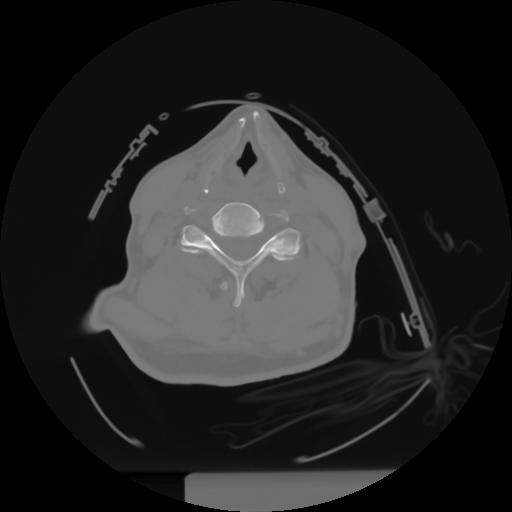

10 P.BLANDAS,,Axial,2.0,P.BLANDAS,,